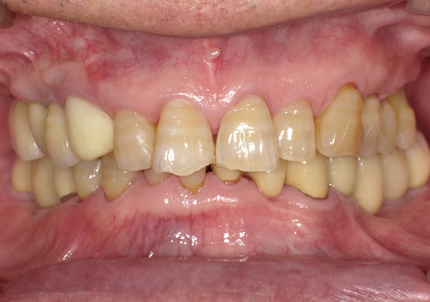

1.初診時口腔内(2007年6月30日)

8.初診より現在に至る

強い歯ぎしり、くいしばりで奥歯の歯牙破折、深い虫歯で保存不可能となり全顎治療となる。

↑ 2007年6月30日(初診)